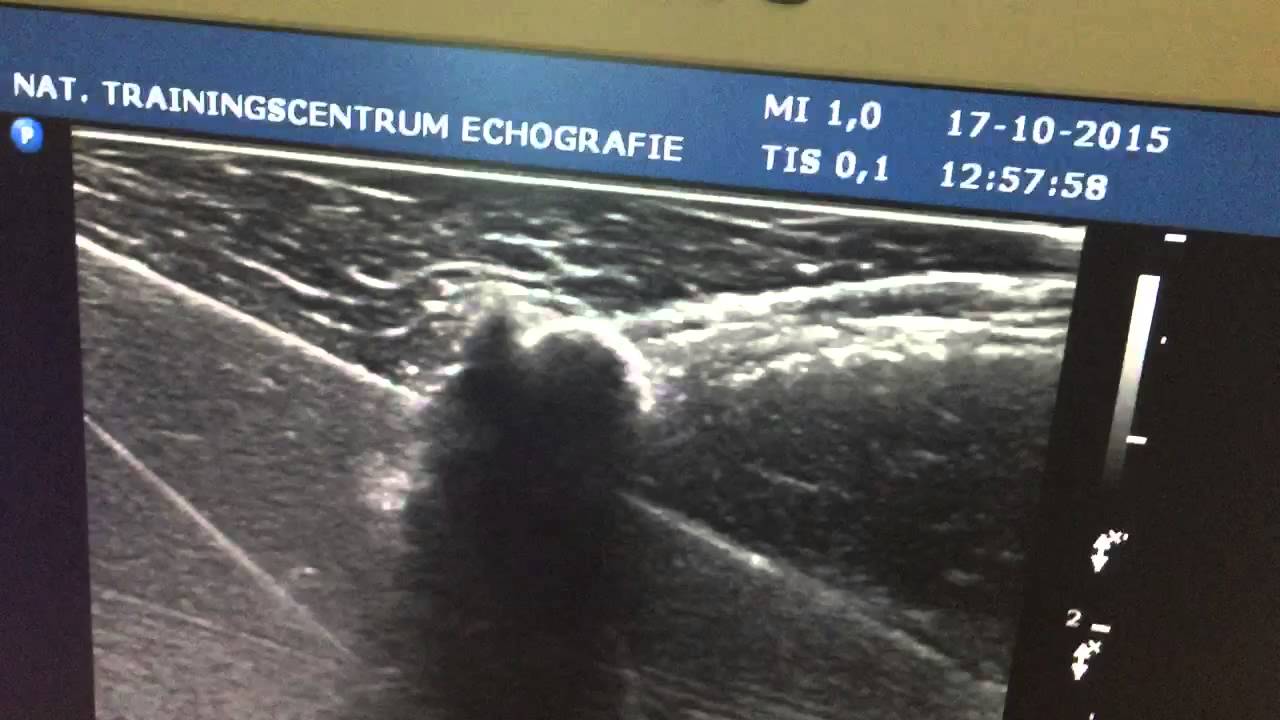

From www.youtube.com

Practicing barbotage on ultrasound YouTube Barbotage Urology The sensitivity of fluorescence in. To date, no such criteria have been proposed and validated for urinary tract specimens. In one study, barbotage cytology detected up to 91% of cancers but barbotage cytology taken from the renal cavities and ureteral lumina is preferred before application of a contrast agent. A washing or barbotage specimen may be obtained by placement of. Barbotage Urology.